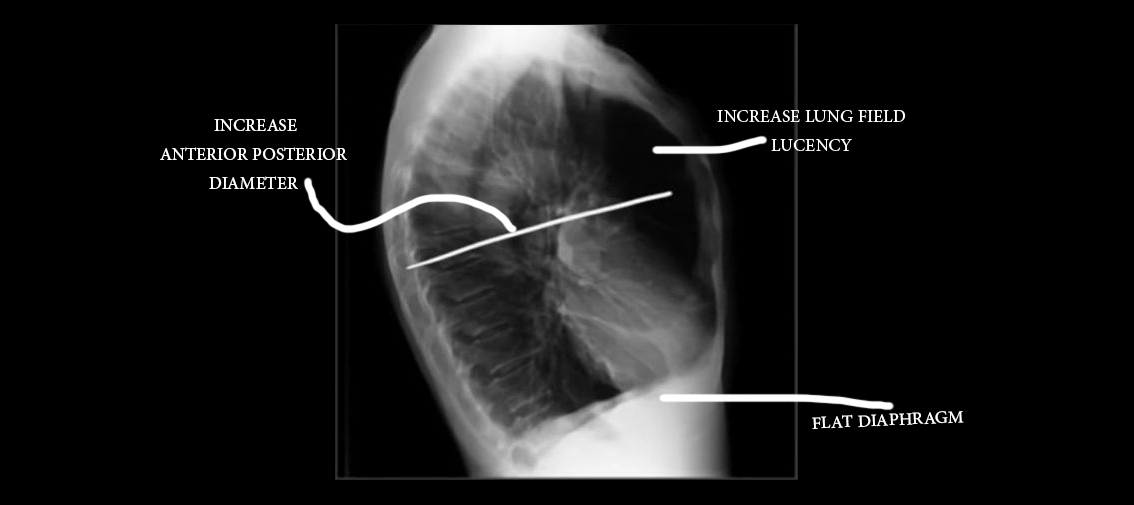

Emphysema Chest X Ray

Low set diaphragm Flat diaphragm best determined by lateral chest Hyper What Causes The Barrel Chest In Emphysema In the form of copd known as emphysema, there. It is a serious condition that gets worse over. However, this post is concerned with barrel chests that result from chronic respiratory conditions, such as emphysema and severe asthma. Barrel chest is a rounded, bulging chest that is similar in shape to a barrel. Emphysema, a type of copd, is one. What Causes The Barrel Chest In Emphysema.